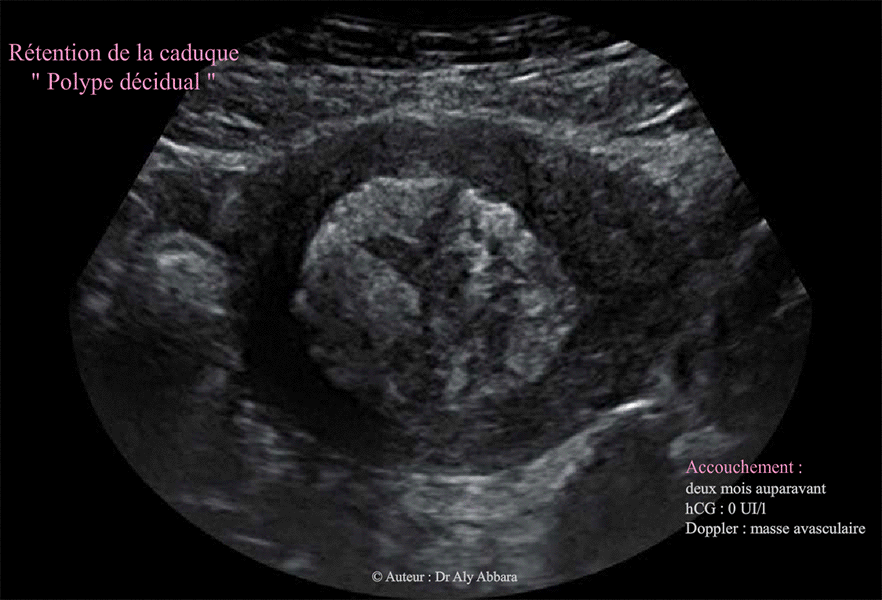

Polype décidual en post-partum ou rétention de la caduque endmétriale en post-partum (accouchement deux mois auparavant

Images échographiques montrant l'aspect d'une masse retenue dans l'utérus suite à un accouchement à terme survenant deux mois auparavant.

La délivrance était artificielle pour non décollement placentaire.

Cliniquement : métrorragie persistant et intermittente depuis l'accouchement ; utérus restant volumineux, mal involué.

Le dosage de hCG plasmatique est égale à zéro témoignant de l'absence d'activité trophoblastique au niveau de cette masse tissulaire retenue dans la cavité utérine.

L'échographie, masse de 45 x 42 x 35 mm de diamètre (soit 34 cm3 de volume) ; elle est hétéroéchogène occupant l'ensemble de la cavité utérine, et au Doppler couleur, il n'a pas été mis en évidence d'un flux sanguin au niveau de cette masse (elle avasculaire).

Après évacuation chirurgical, l'examen anatomopathologique montre qu'il s'agit d'un ensemble de caduque nécrotico-hémorragique associé à des quelques villosités prenant un aspect momifié avec du trophoblaste prenant un aspect fantomatique. Il existe de nombreuses calcifications.

En conclusion : débris de caduque nécrotique (polype décidual nécrotique) et villosités momifiées.